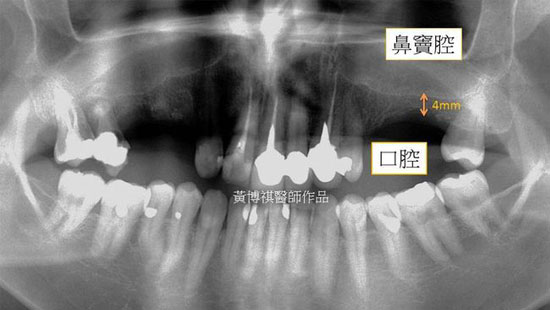

口腔上顎後牙區僅有薄薄一層上顎骨與鼻竇腔相隔,若要在此部位進行植牙手術重建咬合功能, 必須先進行鼻竇增高術,以期植體獲得最佳穩定度。 |

手術區域為上顎後牙區,先游離上顎骨後,進入鼻竇腔進行骨再生術式術後X光片可見上顎骨墊 出一層厚厚的新骨,術後一年追蹤,骨細胞逐漸生成新的上顎骨。 |